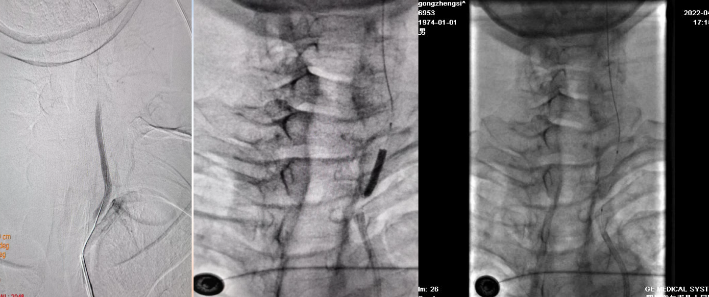

术前检查

病历夹什么径技·第152期|串联营病历夹:川陕大营_https://www.jmylbn.com_新闻资讯_第59张

病历夹什么径技·第152期|串联营病历夹:川陕大营_https://www.jmylbn.com_新闻资讯_第60张

病历夹什么径技·第152期|串联营病历夹:川陕大营_https://www.jmylbn.com_新闻资讯_第61张

<<滑动查看下一张图片>>

初步诊断:1.脑梗死(右)急性期2.右侧颈内动脉起始部次全闭塞3.右侧大脑中动脉M1段血栓形成

手术过程

1、8F导引导管到位后造影,见右侧颈内动脉起始部闭塞,微导丝及微导管穿过闭塞端,微导管造影确认真腔后,交换出微导管。

病历夹什么径技·第152期|串联营病历夹:川陕大营_https://www.jmylbn.com_新闻资讯_第62张

2、将BostonScientificSterlingMR2.5*20mm球囊置于右侧颈内动脉起始部,将压力打至8个大气压。

病历夹什么径技·第152期|串联营病历夹:川陕大营_https://www.jmylbn.com_新闻资讯_第63张

3、小球囊扩张后见右侧颈内动脉起始部重度狭窄,右侧大脑中动脉分叉处血栓形成。

病历夹什么径技·第152期|串联营病历夹:川陕大营_https://www.jmylbn.com_新闻资讯_第64张

4、使用6F中间导管抽吸后,右侧大脑中动脉血流通畅。

病历夹什么径技·第152期|串联营病历夹:川陕大营_https://www.jmylbn.com_新闻资讯_第65张

病历夹什么径技·第152期|串联营病历夹:川陕大营_https://www.jmylbn.com_新闻资讯_第66张

5、保护伞到位后,使用BostonScientificSterling MR4.0*30mm球囊扩张,将压力打至14个大气压,造影见右侧颈内动脉起始部狭窄扩张满意。

病历夹什么径技·第152期|串联营病历夹:川陕大营_https://www.jmylbn.com_新闻资讯_第67张

6、右侧颈内动脉起始部置入Carotid WALLSTENT7*40mm自膨式支架,造影见:支架贴壁良好,斑块完全覆盖,血流通畅,管腔打开良好,右侧大脑中动脉血流通畅。支架置入后观察30分钟,支架内血流通畅。